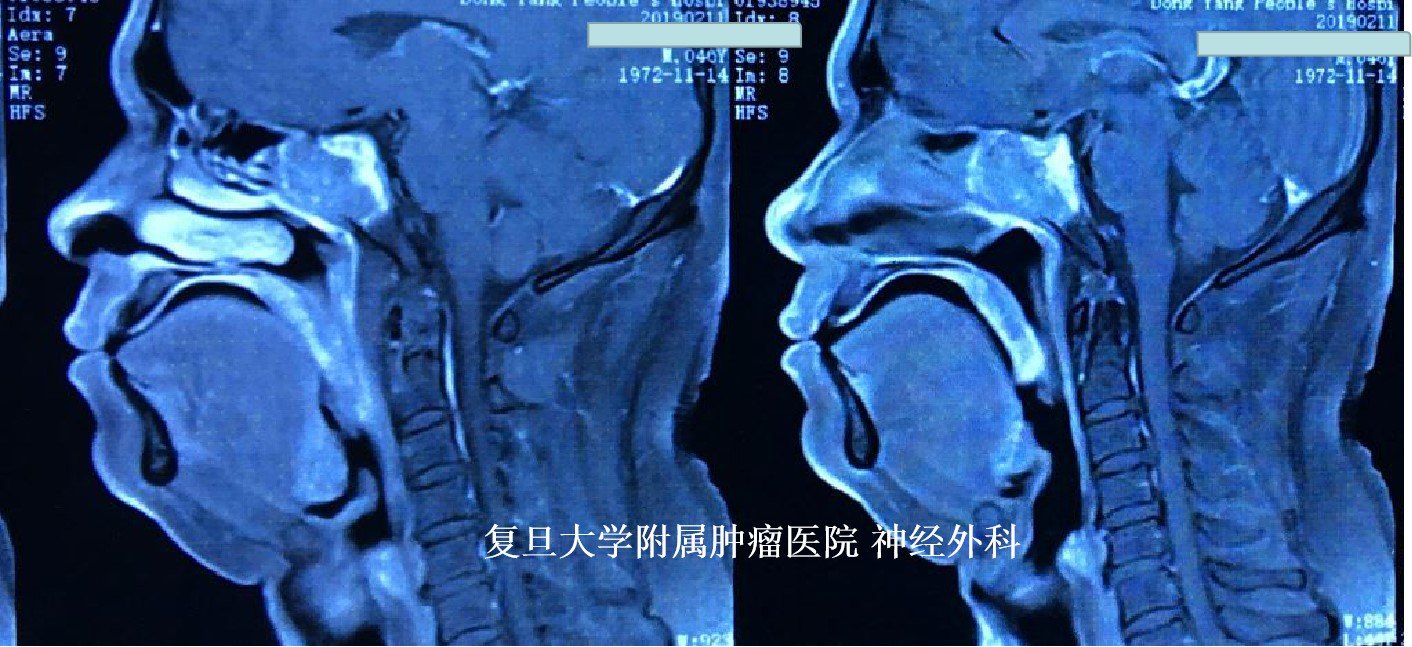

患者为中年男性,头痛头晕3个月,头颅MRI检查示:鞍区占位,主要累及斜坡及蝶窦,侵袭性生长,有强化,周边重要神经血管结构受累,考虑恶性肿瘤可能。